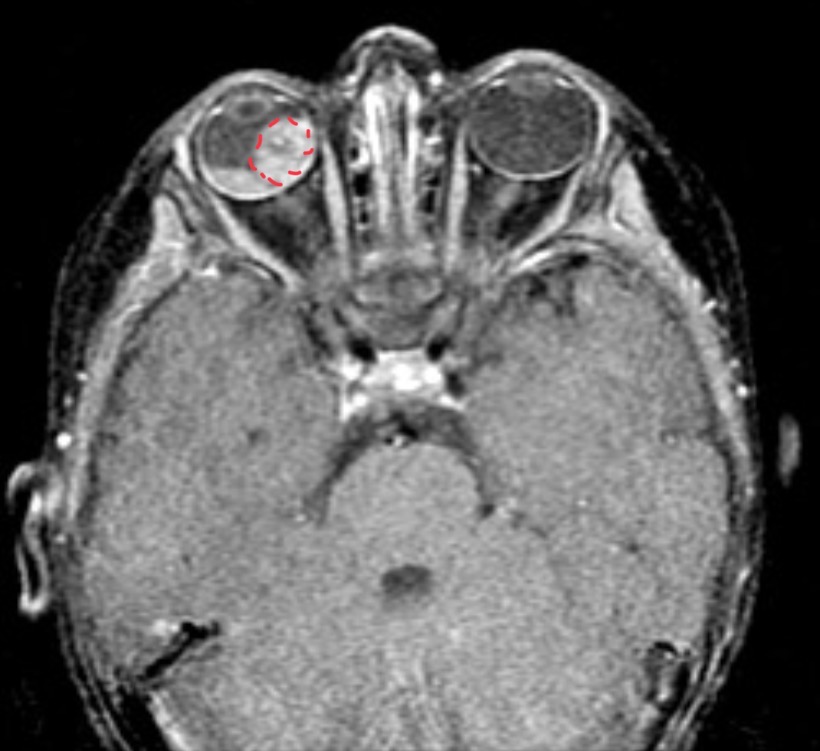

Child presents with no available information

Retinoblastoma w retinal detachment